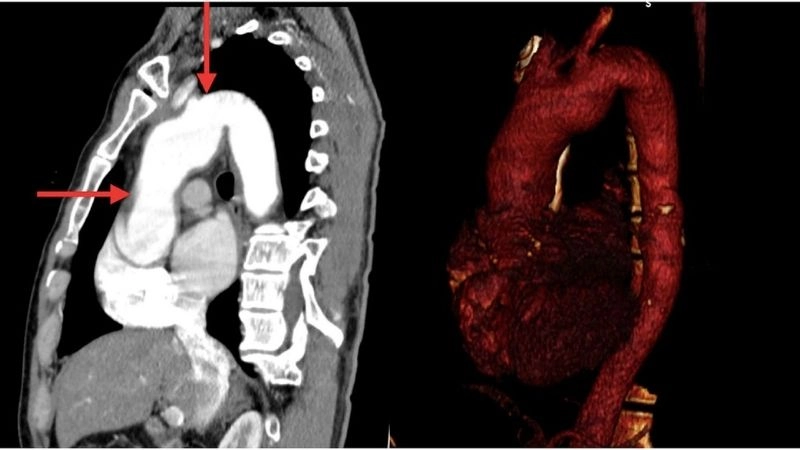

Aortic aneurysm as a complication of aortitis